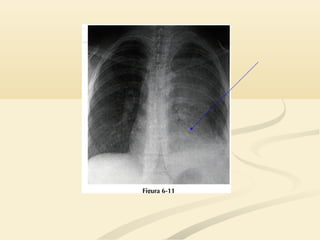

 La consolidación del LSD causará un signo de la siluetaLa consolidación del LSD causará un signo de la silueta

en el borde cardíaco derecho superior y en la interfaseen el borde cardíaco derecho superior y en la interfase

traqueopulmonar derecha.traqueopulmonar derecha.

 El LSDocupa el tórax anterior y medio por encima deEl LSD ocupa el tórax anterior y medio por encima de la cisura menor.la cisura menor.  La consolidación del LSD causará un signo de la siluetaLa consolidación del LSD causará un signo de la silueta en el borde cardíaco derecho superior y en la interfaseen el borde cardíaco derecho superior y en la interfase traqueopulmonar derecha.traqueopulmonar derecha.